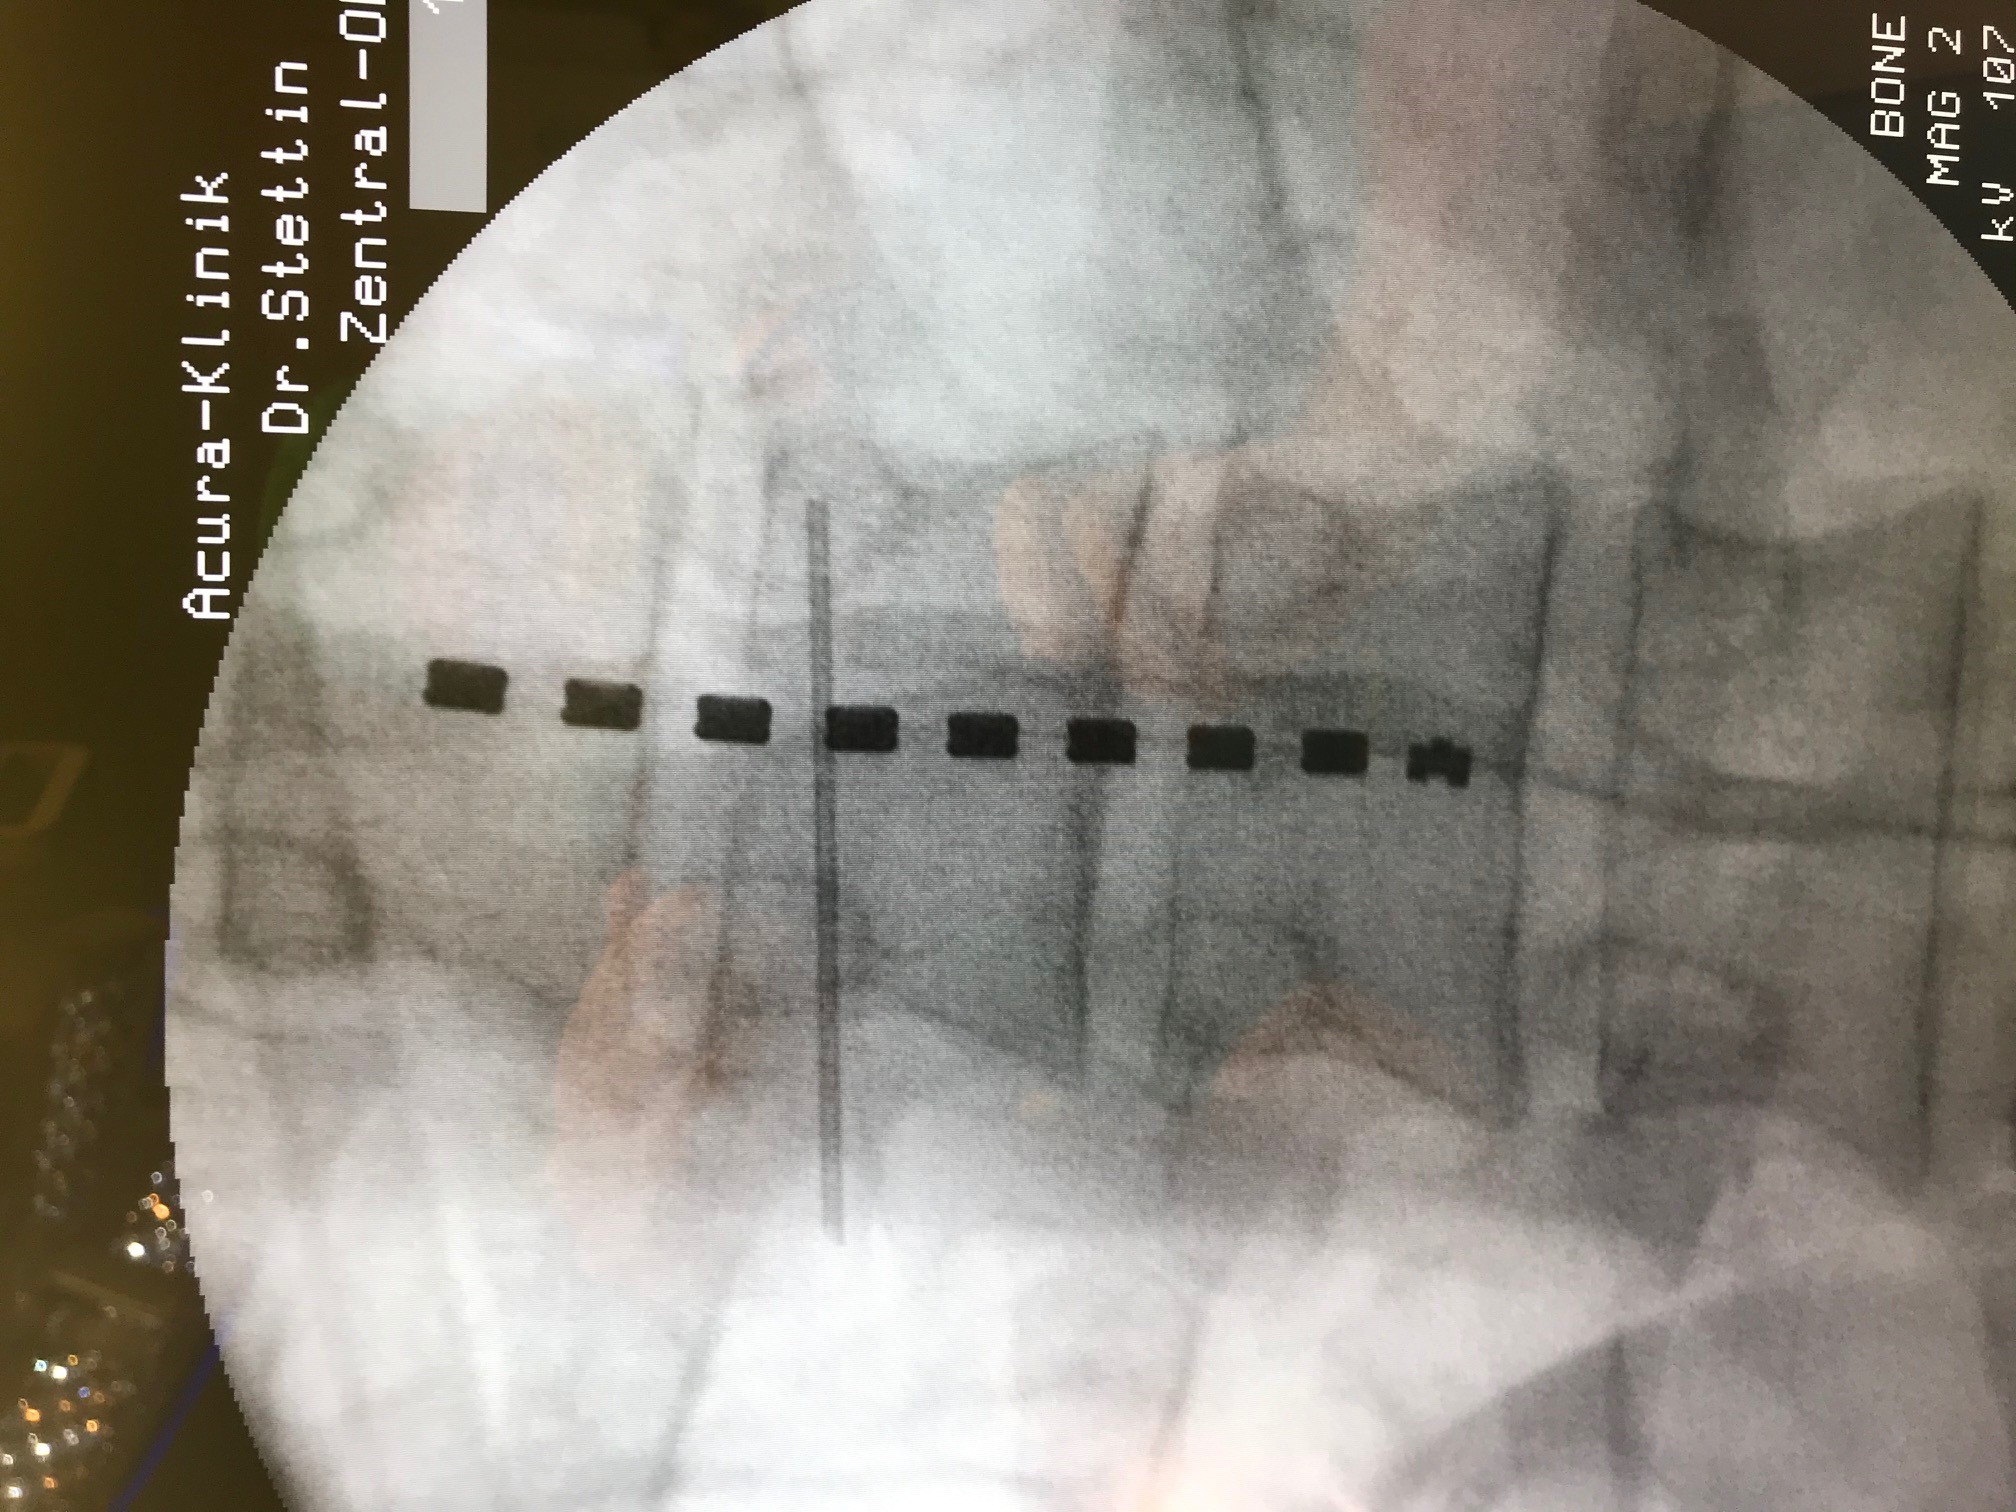

as Verfahren wird Neuromodulation genannt (SCS – Spinal Cord Stimulation). Über eine minimalinvasive Operation wird eine Elektrode auf das Rückenmark aufgelegt und hierüber die Bahnen, welche für die Schmerzweiterleitung zuständig sind, beeinflusst.

Die Bilder zeigen einen 31 jährigen Patienten, der in der Vorgeschichte bereits 2 Mal aufgrund eines Bandscheibenvorfalls operiert wurde.

Bereits vor beiden Operationen bestanden ein Taubheitsgefühl und eine Schwäche für die Fußmuskulatur. Nach dem zweiten Eingriff bestanden weiterhin Schmerzen im Bein.

In einem dann durchgeführten MRT zeigte sich jedoch, dass der Nerv völlig frei war und nicht mehr durch Bandscheibengewebe gedrückt wurde. Nach weiterer erfolgloser konservativer Therapie (Reha, Medikamente und Infiltrationen) bestand dann die Indikation für einen Schmerzeingriff.

Auf den Bildern sehen Sie die Anlage einer Elektrode im Spinalkanal. Die Elektrode wird, unter Röntgenkontrolle auf der Haut die das Rückenmark umgibt, eingebracht und so weit nach oben geschoben, dass sie auf dem Areal zu Liegen kommt in dem die Schmerzen der Beine im Rückenmark verschaltet werden. Über ein hier aufgebautes elektromagnetisches Feld wird direkt auf die Schmerzweiterleitung eingewirkt und die Schmerzen im Bein werden „blockiert“.